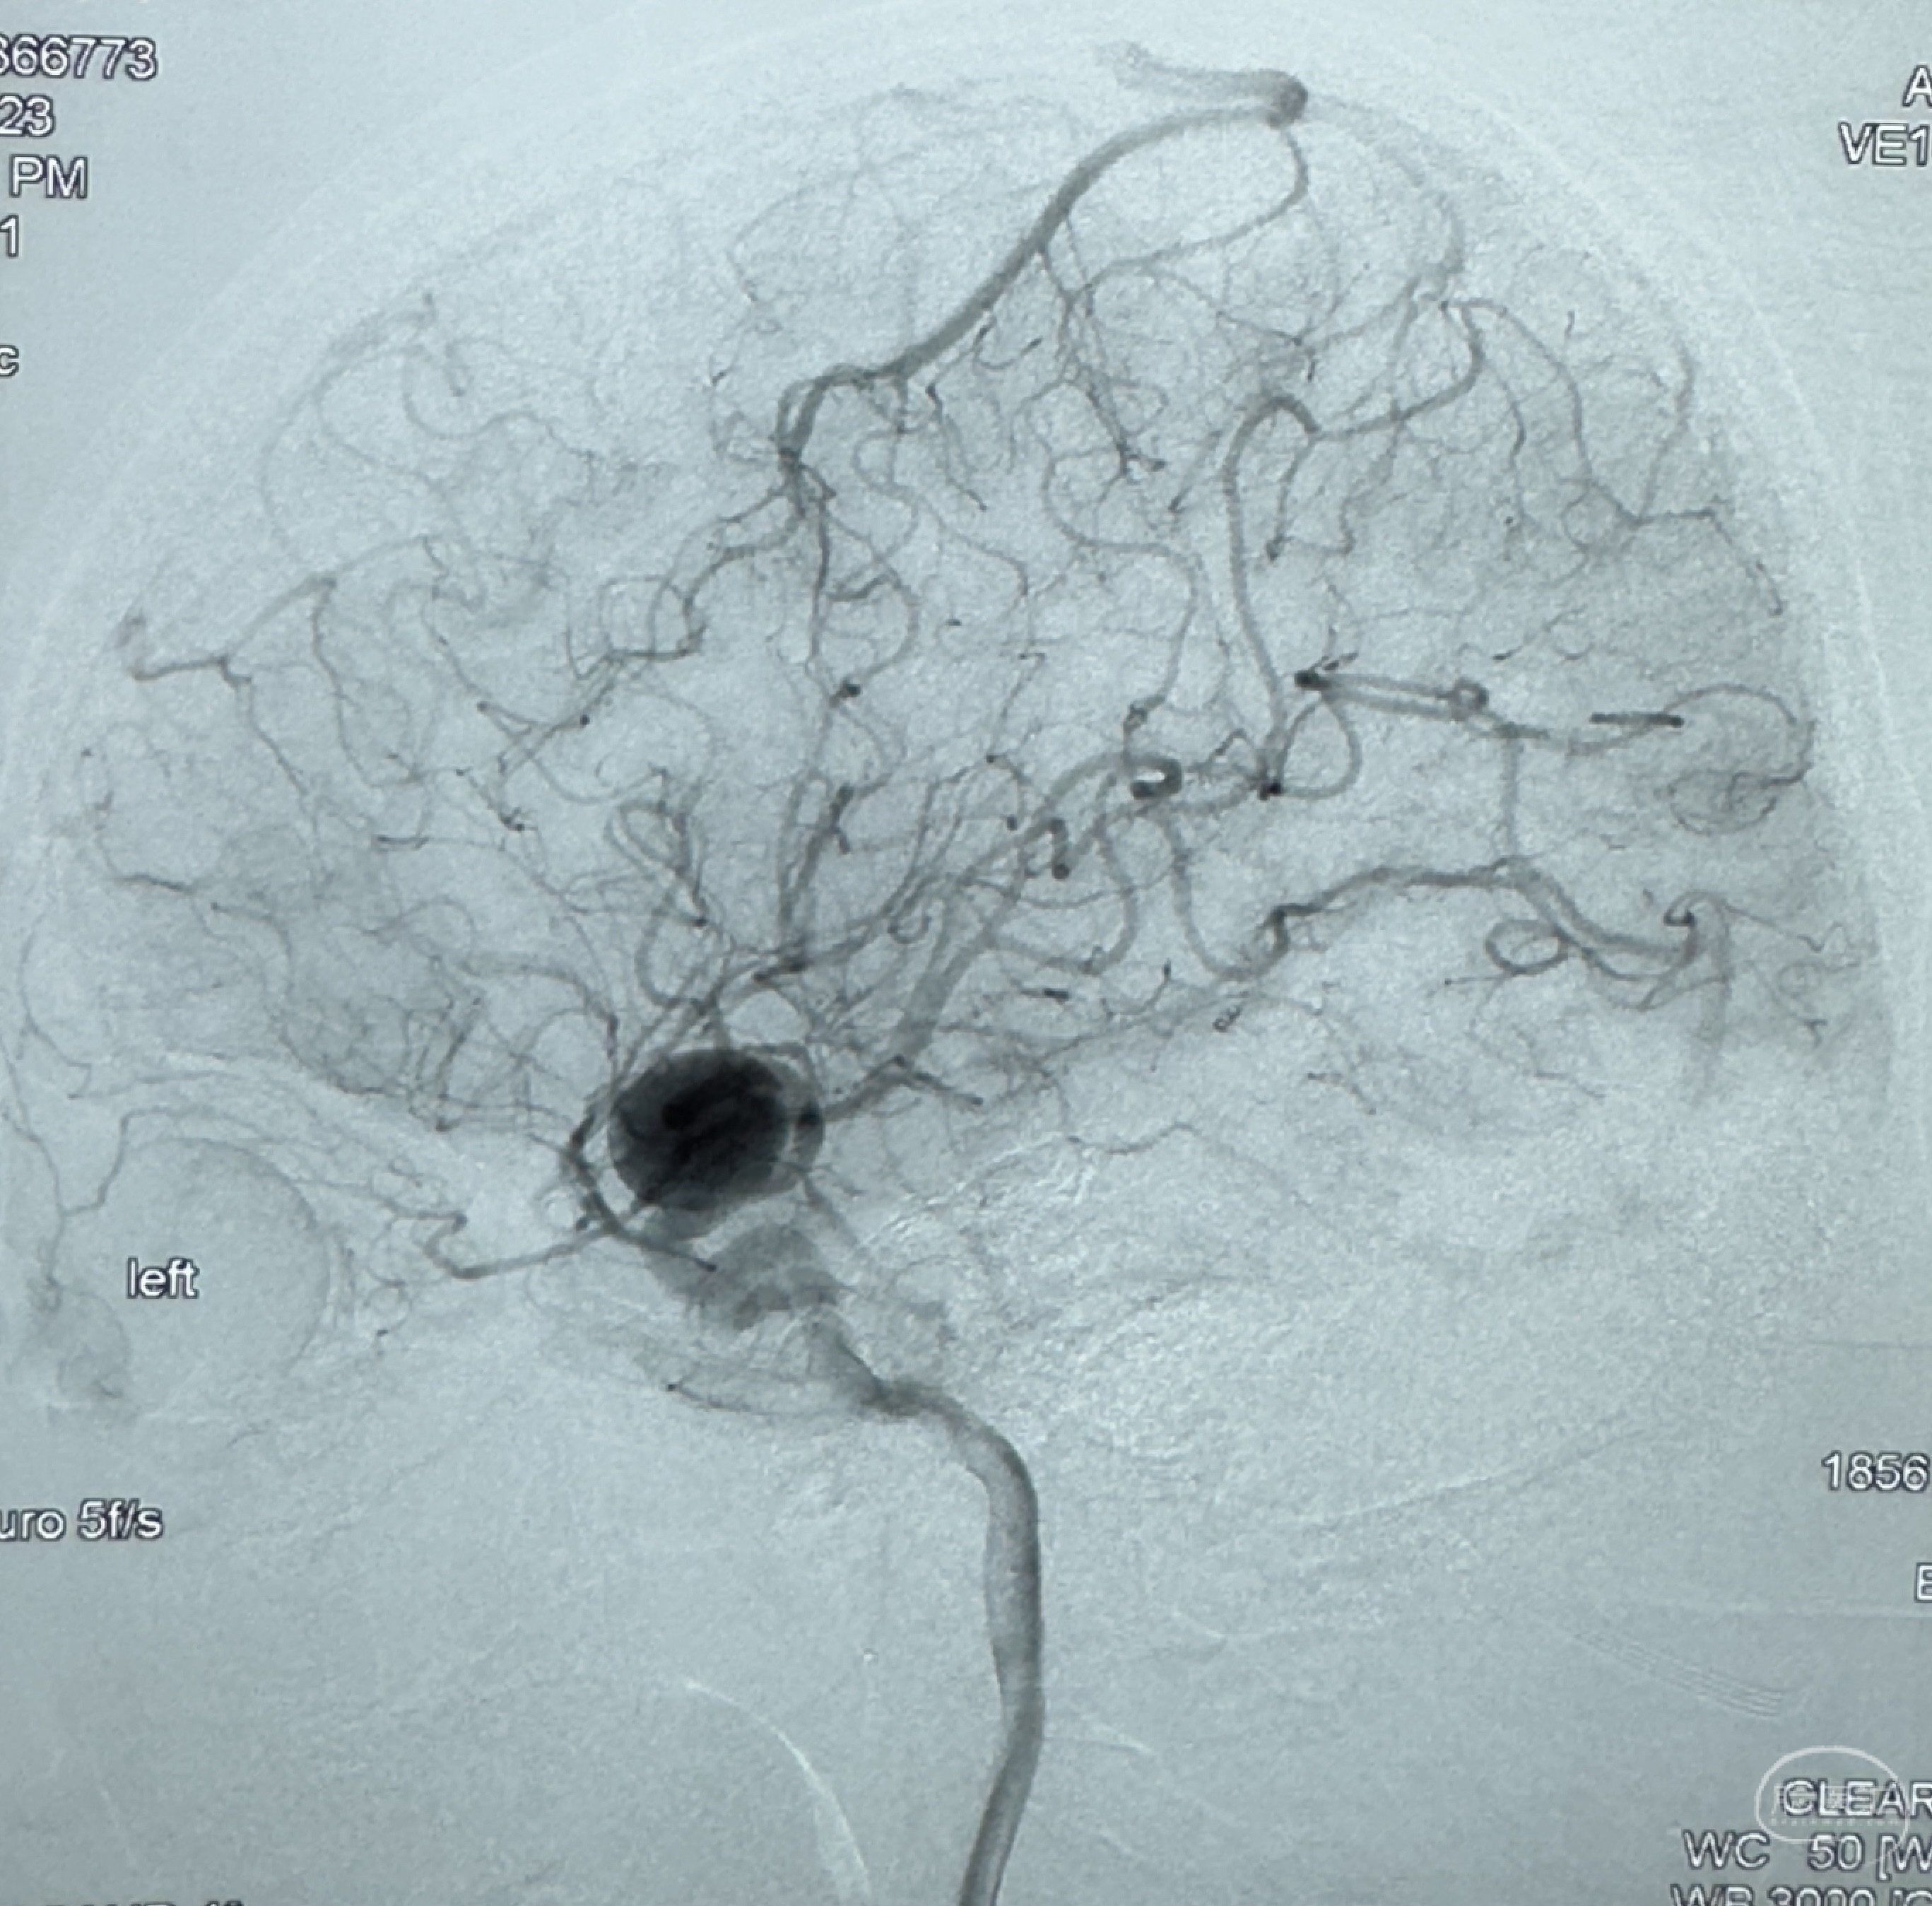

2023-12-27术后第十天复查DSA

支架贴壁佳,但可见射流,咋办?

2024-01-08全麻下再行植入密网支架一枚

Tubridge 4.5-35mm

支架植入顺利,贴壁佳,支架内血流通畅,动脉瘤内血液滞留明显